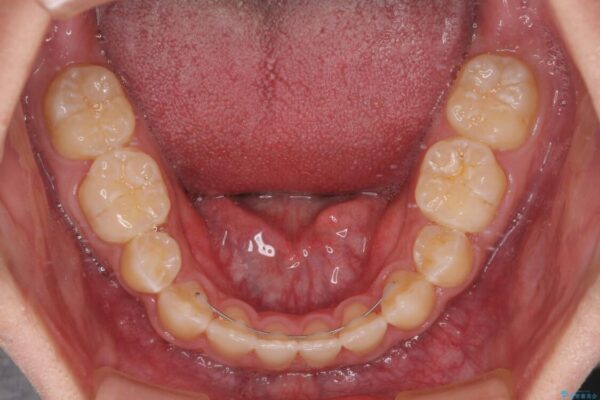

治療後

• 口元の突出感を改善 受け口傾向の咬み合わせの抜歯矯正 治療後画像